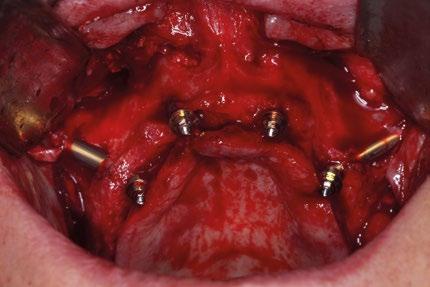

La planificación comienza con un CBCT para evaluar la densidad ósea del cuerpo cigomático, región pterigoidea y pared lateral de la cavidad nasal. Se realiza incisión crestal o vestibular extendida con colgajo mucoperióstico para exponer el reborde residual. Los implantes

cigomáticos se colocan con angulación hacia el cuerpo del cigoma desde el sector premolar, con perforación bicortical. Es esencial el estudio imagenológico con CBCT y escaneado intraoral para confeccionar una guía quirúrgica específica. En este caso se realizó una planificación virtual con software 3D para determinar la trayectoria ideal de los implantes transnasales y cigomáticos, asegurando que los ejes emergentes coincidan con el futuro diseño protésico.

Para los implantes transnasales se diseñó una guía quirúrgica impresa en resina que permite perforaciones precisas desde la cresta alveolar hacia la pared lateral nasal a una angulación de 30–45°, evitando penetración hacia la cavidad nasal sin dejar de despegar sus respectivas membranas y su correspondiente injerto. Esta guía se soporta en el reborde maxilar remanente con base en biomodelos impresos también en 3D.

Procedimiento quirúrgico

Se levanta un colgajo de espesor total con incisiones vestibulares amplias. Se exponen las zonas de reborde alveo -

lar, tuberosidad y cuerpo cigomático. Se despega la membrana nasal bilateralmente para evitar perforaciones de esta y se coloca creos™ xenogain de Nobel Biocare, un material de injerto óseo hecho de hueso bovino purificado. Con ayuda de la guía, se realizan las perforaciones transnasales hasta alcanzar la cortical nasal, obteniendo estabilidad tricortical. Posteriormente, se retira la guía y se colocan los implantes.

Para los implantes cigomáticos NobelZygoma, se realiza osteotomía bicortical con fresas de bola y calibradas hasta alcanzar el cuerpo del cigoma. El implante se introduce con torque elevado, asegurando anclaje en la cortical cigomática. Los implantes pterigoideos se colocan posteriormente con angulación de 70–75° hacia la placa pterigoidea, favoreciendo estabilidad tricortical.